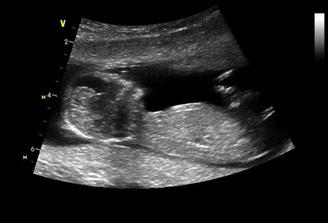

23.6.2009 dle utz 6+4 tt, dvě bušící srdíčka, předběžný termín porodu 15.2.2010,

30.6.2009 dle utz 7+3 tt, stále dvě bušící srdíčka,

14.7.2009 dle utz A 10+0tt, B 9+4tt, u obou aktivní pohyb 🙂termín porodu upřesněn na 11.2.2010, a 4.8.jdu na NT screening -dopadl skvěle, jsme 13+0tt, obě stejně velká, termín 9.2.2010

23.9.velký ultrazvuk